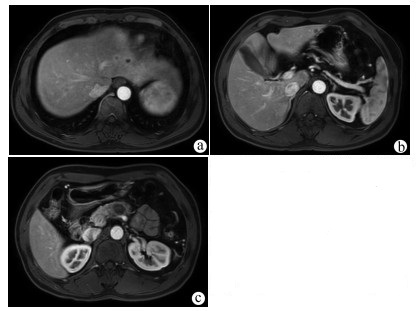

Lymphoepithelioma-like hepatocellular carcinoma: A case report

Xiaotong QIU, Zhengqi WU, Xuxiang XIA, Guoyue LYU

2022, 38(3): 634-635. DOI: 10.3969/j.issn.1001-5256.2022.03.027

Abstract(762) HTML (934) PDF (2924KB)(68)

Abstract: